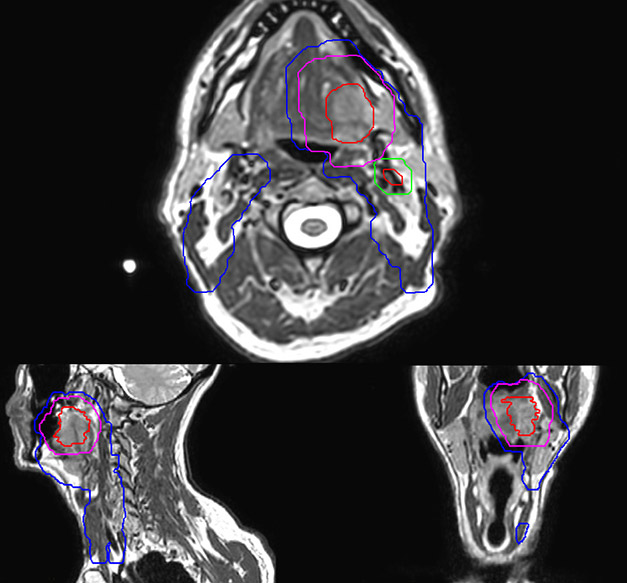

Epidermoid carcinoma of the left tongue base

The patient was diagnosed with an epidermoid carcinoma of the base of the left invading the amygdala lodge and the amygdaloglossal groove. Radiochemotherapy with curative aim was prescribed with a dose of 70 Gy for the tumor, 66 Gy on the suspicious nodes and 56 Gy on the elective drainage areas - in 33 fractions.

MR-based target contouring on 3D T2W TSE in transversal, sagittal and coronal planes.